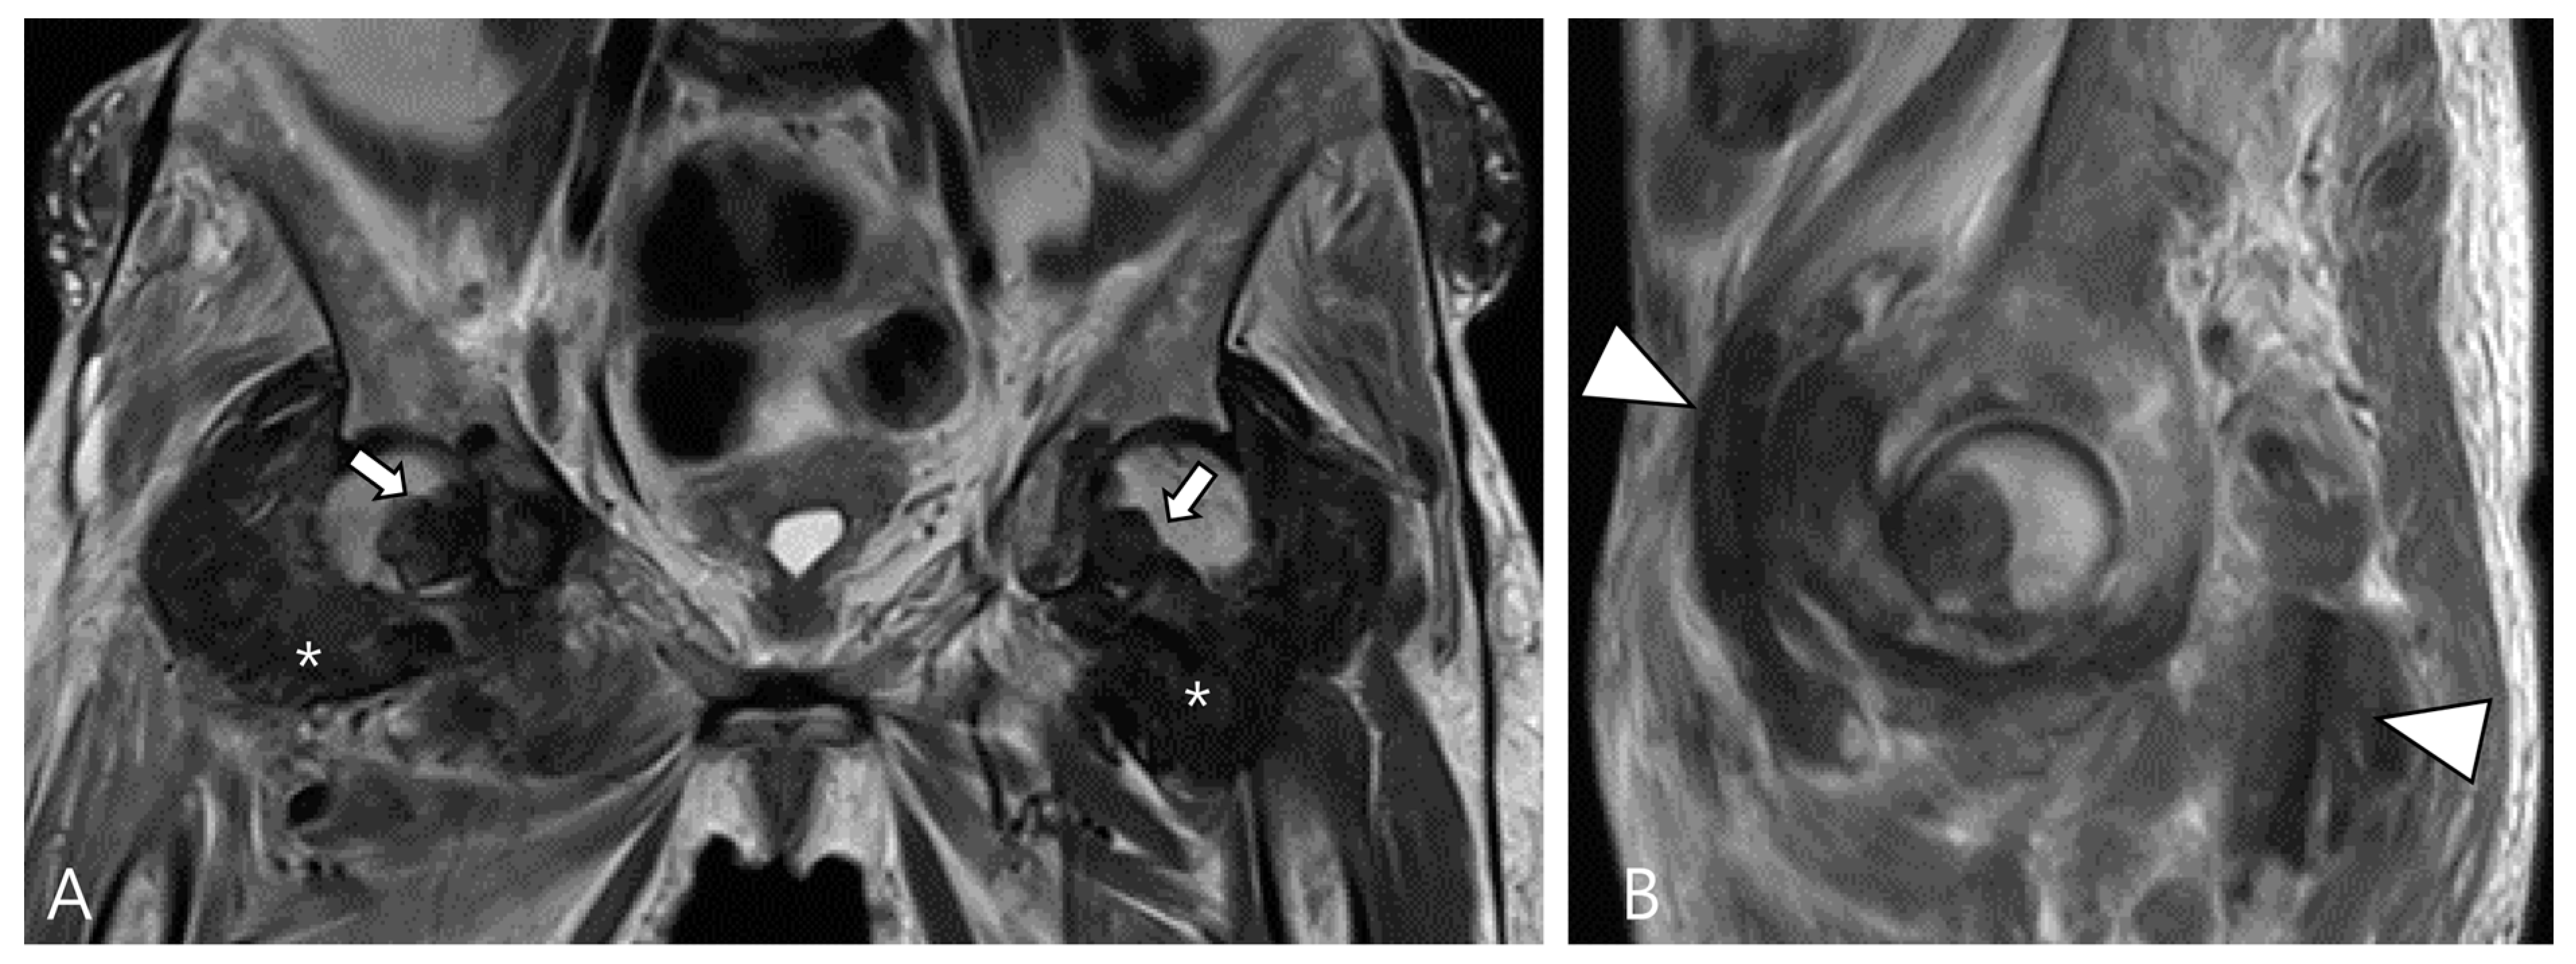

3.1. Differential Diagnoses of Intra-Articular D-TSGCT

3.1.1. Hemosiderotic Synovitis

3.1.3. Dialysis-Related Amyloid Arthropathy